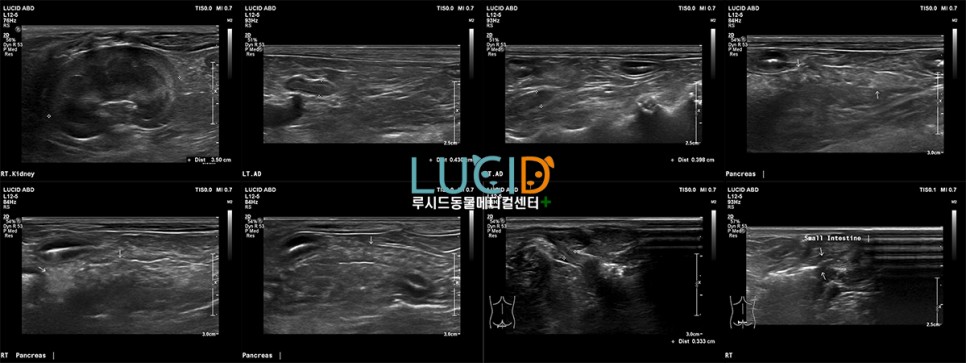

고령 어린이의 나이를 고려하여 기본 건강검진 항목인 신체검사, 혈액검사, 흉복부 방사선, 복부초음파에 심장초음파 항목이 추가되어 진행되었습니다.

복부 초음파로 확인되는 것은 양쪽 신장 내의 결석이 확인되며, 요관-방광-요도 내의 결석은 없는 것으로 보입니다.신장 내 결석도 주기적인 체크를 통한 변화 확인이 필요합니다.

담낭 내의 슬리지가 확인되지만, 담낭 점액종으로 가는 진행 정도는 미미한 정도입니다.간 실질 이상 소견은 없지만 주기적인 담낭상의 변화 여부 확인을 권장합니다.

우측 회음부의 회음탈장이 확인되었고 초음파상 복강장기(소장)의 탈출이 확인되었습니다.근본적으로는 수술적인 방법에 의한 교정이 필요할 것으로 보이며 결손부가 넓어지면 더 큰 사이즈로 확인될 수 있습니다.